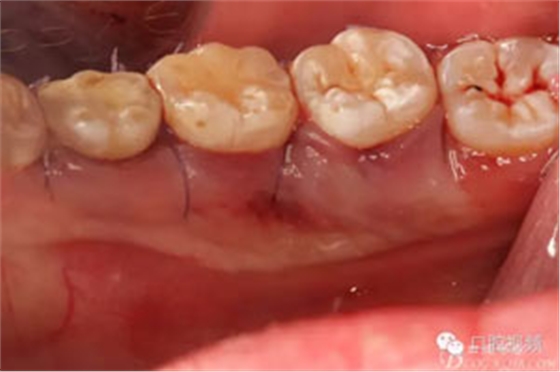

圖13.縫合,舌側(cè)組織輕度反應(yīng)